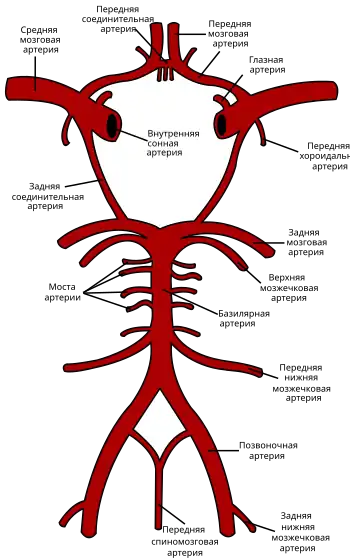

Виллизиев круг и артерии головного мозга. Задние мозговые артерии (нижние ответвления) берут начало от основной артерии (в центре). | |

Парные задние мозговые артерии — левая и правая — это артерии, которые кровоснабжают заднюю часть головного мозга у человека (теменную долю конечного мозга) и формируют часть Виллизиева круга. Задняя мозговая артерия каждой стороны находится возле пересечения соответствующей задней соединительной артерии c основной артерией. Каждая из двух задних мозговых артерий соединяется с соответствующей средней мозговой артерией и с соответствующей внутренней сонной артерией при помощи соответствующей задней соединительной артерии.